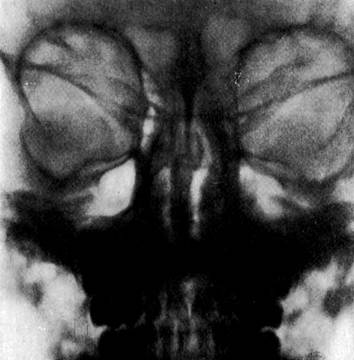

Рис2. Затемнение левого решетчатого лабиринта.

Наблюдение: ебенок Т.,6 лет, заболел внезапно. Температура 38.5°. Объективно: краснота и отек век левого глаза. Главная щель сужена (рис. 1). Со стороны главного яблока отмечается отек конъюнктивы; роговица и среды прозрачны, главное дно нормально. Гной в среднем ходе носа. Нf рентгенограмме - левосторонний этмоидит (рис. 2) Под влиянием консервативного лечения (тепло и носовые турунды из кокаин-адреналина) нос очищается и все патологические явления со стороны левого глаза ликвидируются.